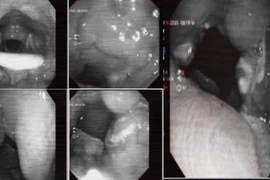

Hình ảnh nội soi thấy được dị vật làm nghẽn đường thở. Ảnh BV/ Nguồn báo Cần Thơ

Sau hội chẩn với Khoa Hồi sức tích cực - Chống độc, ê-kíp nội soi phế quản do bác sĩ Phan Thanh Thông thực hiện đã tiến hành nội soi cấp cứu. Dị vật là nửa quả nho xanh bít hoàn toàn phế quản gốc trái. Bằng thao tác chính xác, bác sĩ đã gắp thành công dị vật, giải phóng đường thở và cứu bệnh nhân khỏi tình trạng nguy hiểm.